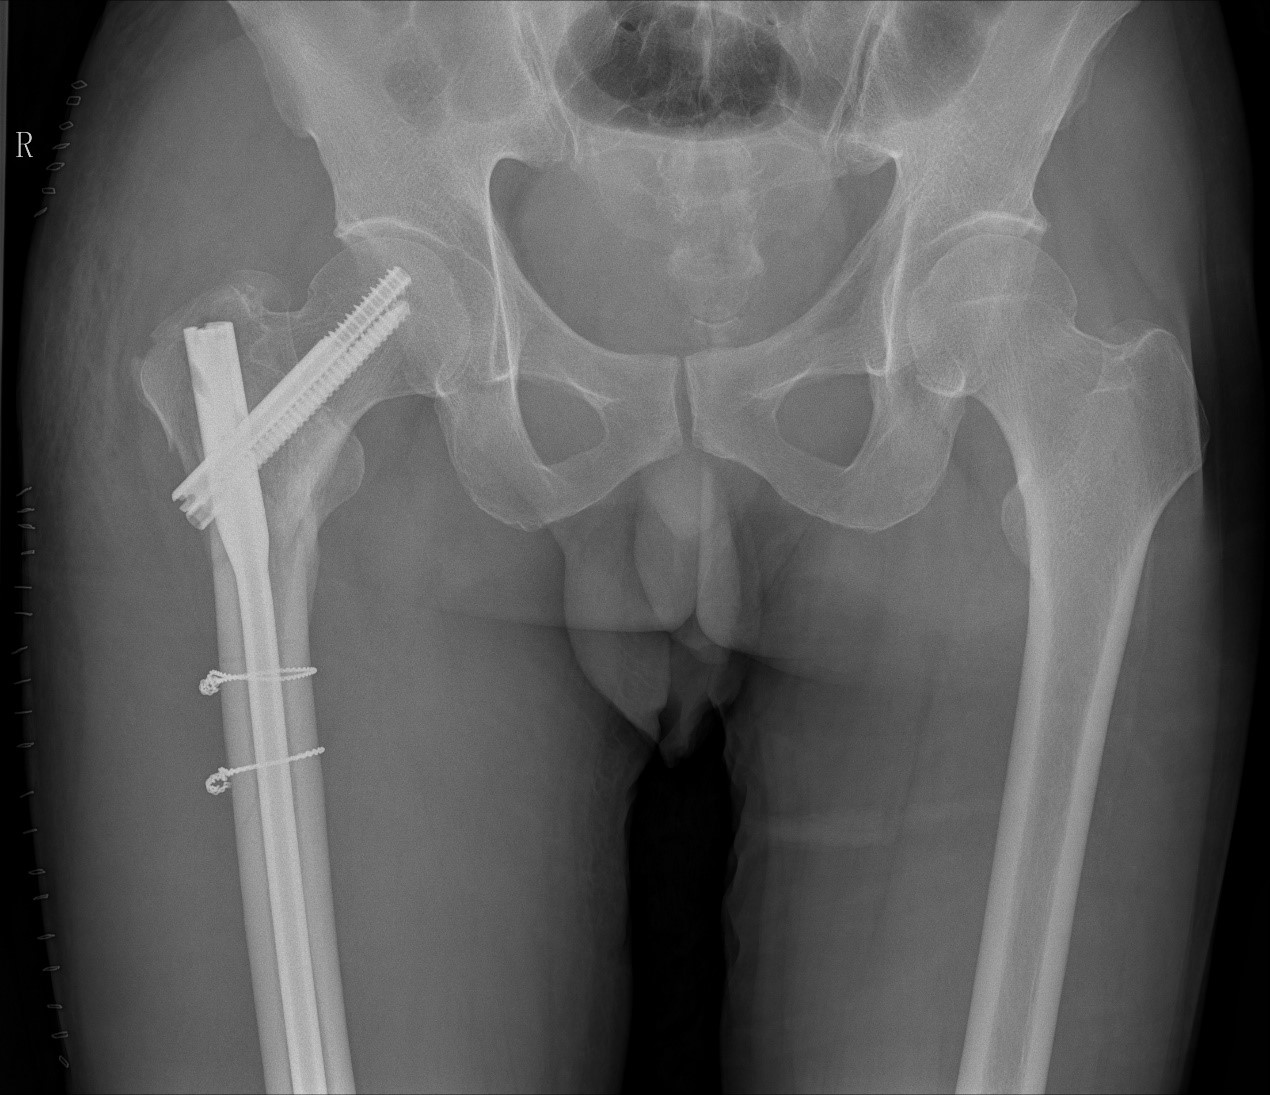

案例二:51岁男性意外摔伤

患者情况:吴先生因路面湿滑不慎摔倒,导致右髋部疼痛并活动受限,经检查确诊为股骨粗隆间骨折。

治疗难点:

1.骨折部位解剖重建的准确性;

2.内固定材料的选择及固定强度的保障。